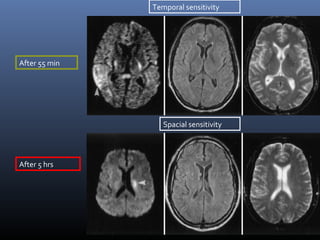

DWI- stroke

 Hyperacute stroke- Cytotoxic edema

 Lesion appears bright

Temporal sensitivity

Spacial sensitivity

After 55 min

After 5 hrs